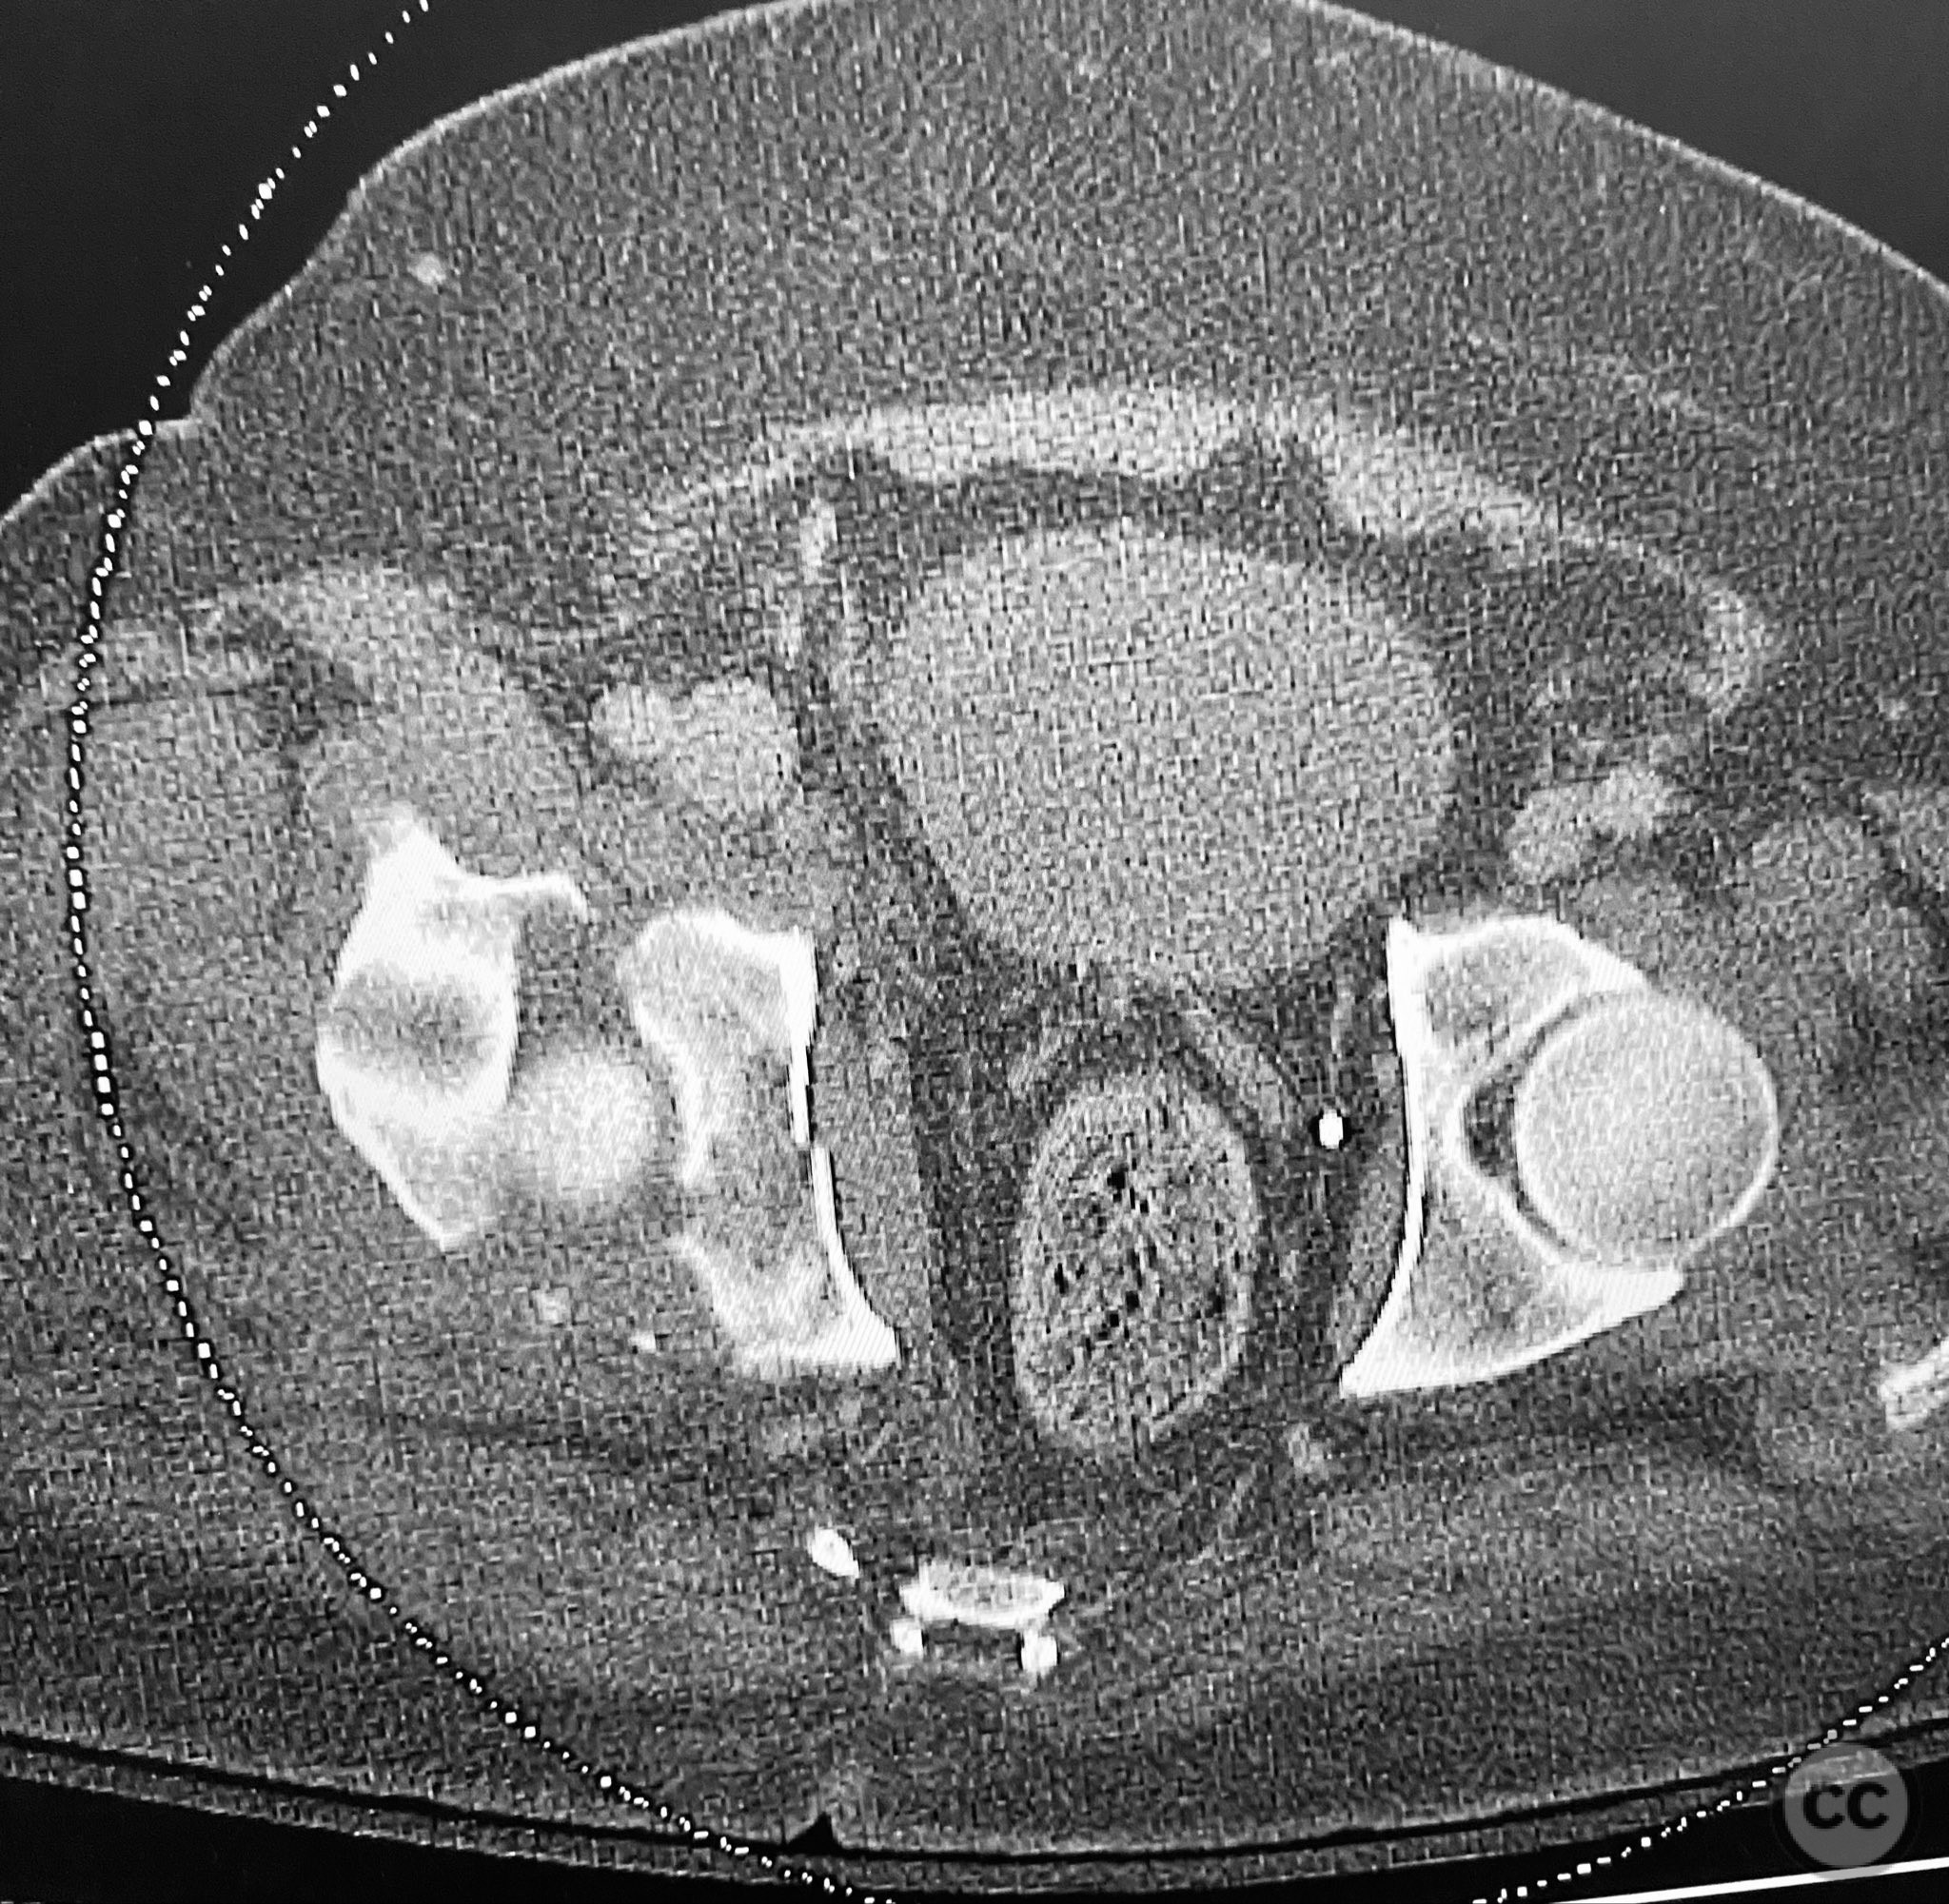

Clinical and radiological findings:  A 79-year-old male sustained a high-energy injury in a motor vehicle collision, resulting in a complex acetabular fracture-dislocation. Radiographs and computed tomography demonstrated a posterior wall and transverse acetabular fracture (AO/OTA 62-B1.3), with the posterior wall fragments displaying an atypical caudal hinge configuration. The medial wall fragment was non-articular. Axial imaging revealed an impacted osteochondral fragment obstructing reduction, as well as disruption of the capsular structures adjacent to the intact articular segment. The obturator internus tendon appeared taut but intact, with no evidence of sciatic nerve impingement or superior gluteal neurovascular compromise.

Anatomical surgical approach:  A standard Kocher-Langenbeck approach was performed, incising through the gluteal fascia and splitting the fibers of the gluteus maximus. The short external rotators were identified and protected, with subperiosteal dissection exposing the posterior column and wall of the acetabulum. The sciatic nerve was identified and mobilized laterally. The posterior capsule was found disrupted adjacent to the intact articular surface. The impacted osteochondral fragment was extracted from the joint space. The transverse fracture plane was debrided and reduced using clamps, with a greater trochanteric bone hook employed to manipulate the femoral head beneath the acetabular dome during reduction. Provisional fixation was achieved with a percutaneous lag screw across the transverse component. The peripheral posterior wall fragment was anatomically reduced and stabilized with a contoured plate. The medial wall defect provided access for reduction of the impacted articular segment, which was bone grafted prior to reduction and plating of the medial wall. Capsular tissues were repaired with nonabsorbable sutures prior to layered wound closure.

The posterior wall fragments exhibited an unusual caudal hinge morphology, necessitating careful mobilization to avoid propagation or comminution. Removal of the impacted intra-articular fragment was essential to achieve concentric reduction of the femoral head within the acetabular dome. Use of a greater trochanteric bone hook facilitated precise control of femoral head position during reduction maneuvers. The medial wall fragment, though non-articular, allowed direct visualization and accurate reduction of the impacted osteochondral segment, which was supported with bone graft prior to definitive fixation. Repair of disrupted capsular tissues was performed to restore soft tissue integrity and potentially reduce postoperative instability.